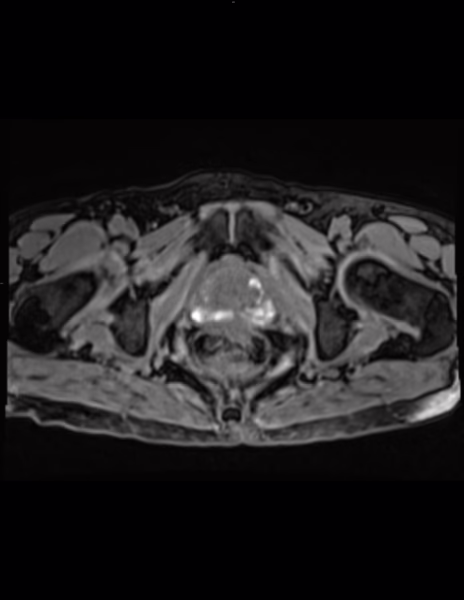

Método de estudio: Resonancia magnética de próstata en secuencias multiplanares en imágenes ponderadas en T2 axial, sagital y coronal, difusión, mapa de ADC, T1 axial, T2-FATSAT e imágenes de contraste dinámicas después de la administración IV de gadolinio.

Se identifican cambios hemáticos dispersos en ambas zonas periféricas evidentes hiperintensidades difusas en secuencia T1 y T1-FATSAT, no muestran restricción hídrica en difusión, relacionado con antecedente conocido.

Lesión #1: Mide: aproximadamente 6 mm.

Serie 5, Imagen 22/30.

Localización: Zona periférica posteromedial derecha a nivel apical (sector RA-PZpm).

PEE: Probabilidad de Extensión extraprostática: grado 0 de 3 (Mehralivand).

T2: Hipointensidad menor a 15 mm y sin extensión extraprostática. Categoría 4/5.

DWI: Marcada hiperintensidad en difusión y marcada hipointensidad en ADC. Categoría 4/5.

DCE: no se observa realce focal temprano.

Sin obliteración del ángulo recto prostático.